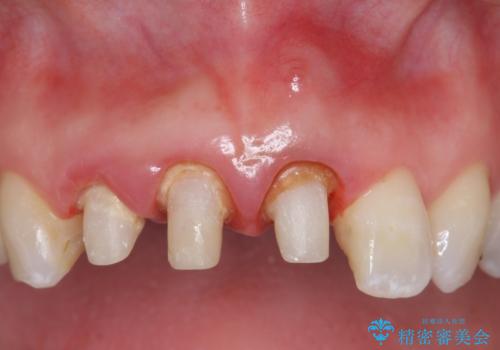

- 前歯の長さが違うのが気になるといらっしゃった方の症例です。

根尖病変を認めたため再根管治療を行った後、オールセラミッククラウン(スペシャル)にて補綴を行いました。

歯肉の腫れをより改善するため歯周外科を提案しましたが希望されませんでした。